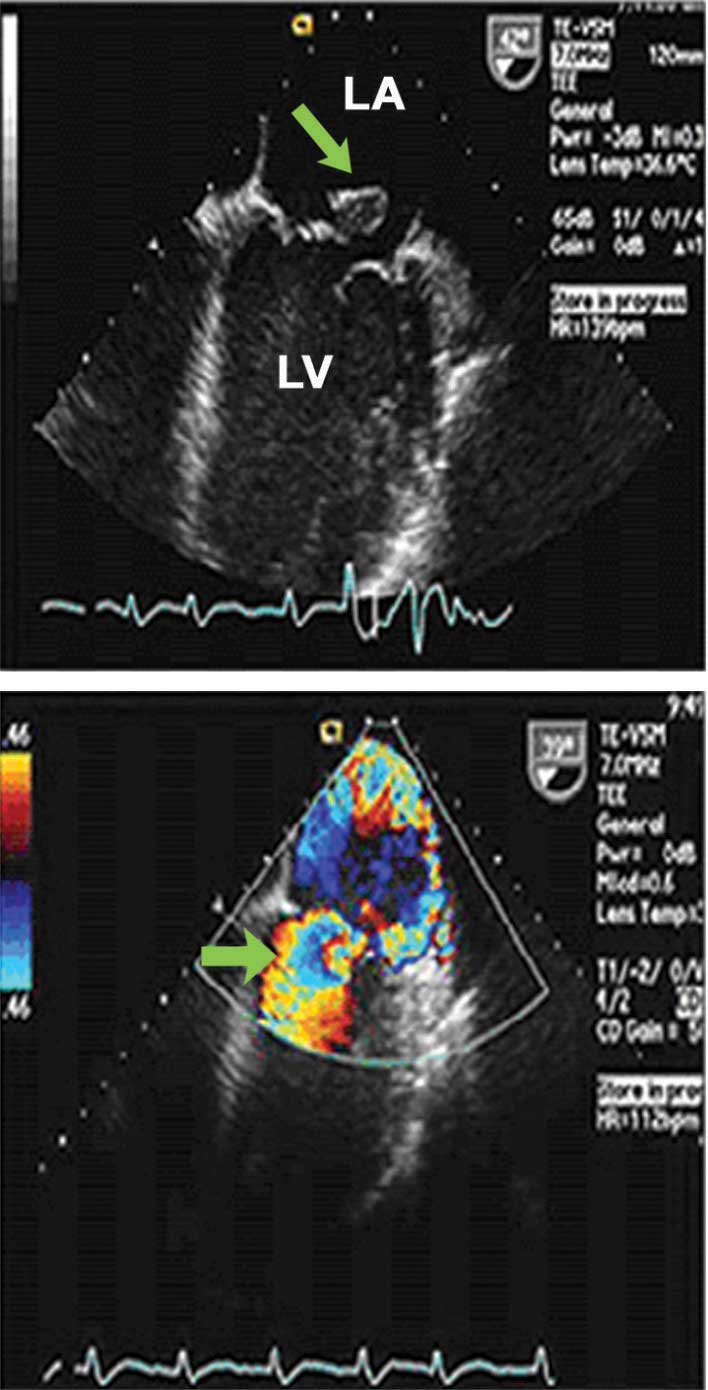

| الشكل (2) تمزق عضلة حليمية كما يبدو في الصورة العلوية، وقلس الصمام المرافق كما يبدو بالدوبلر الملون في الصورة السفلية |

ب- قَلَس (قصور) الصمام التاجي المكتسب acquired mitral regurgitation: ينجم قلس التاجي المكتسب عن أسباب متعددة يعود بعضها إلى وريقات الصمام التاجي كالداء الرثوي والتهاب شغاف القلب والذئبة الحمامية الجهازية والرضوض وغيرها، وينشأ بعضها من إصابة الحلقة الصمامية كما يحدث في اعتلال العضلة القلبية التوسعيdilated cardiomyopathy أو تكلس الحلقة التاجية، ويعود بعضها الآخر إلى إصابة الجهاز تحت الصمامي؛ أي الحبال الوترية والعضلات الحليمية، كما يحدث في التهاب الشغاف، ونقص التروية القلبية واحتشاء العضلة القلبية وغيرها.

يتم تشخيص قلس التاجي كما هو الحال في كل الآفات الصمامية اعتماداً على الصدى والدوبلر. أما تخطيط كهربائية القلب وصورة الصدر البسيطة فلهما دور موجّه للتشخيص وداعم في التقييم من خلال مجموعة من التغيرات كتوسع ضخامة الأذين الأيسر وضخامة البطين الأيسر ووجود الرجفان الأذيني وزيادة التوعية الرئوية. يبقى صدى القلب والدوبلر حجري الأساس في التشخيص وتحديد السبب المؤدي إلى قلس التاجي من خلال تقييم وريقات الصمام والحلقة الصمامية والجهاز تحت الصمامي وفي تقييم وظيفة البطين الأيسر وأبعاده. وتحدد دراسة الدوبلر شدة القلس ودرجة الضغط الرئوي وتؤدي هذه كلها الدور الأهم في تدبير قلس التاجي ووقت التداخل الجراحي. أما تصوير الشرايين الإكليلية والقثطرة القلبية فقد أصبحت ذات قيمة محدودة في التشخيص والتقييم لدقة الصدى القلبي؛ مما جعل دور القثطرة محدّداً في تقييم الشرايين الإكليلية قبل التداخل الجراحي على الصمام التاجي. أما الدراسة بالصدى عبر المريء فقد اكتسبت أهمية واضحة في التقييم عندما تكون الدراسة التقليدية عبر جدار الصدر محدودة الدقة أو لتقييم قابلية الصمام التاجي للإصلاح الجراحي عوضاً عن التبديل.